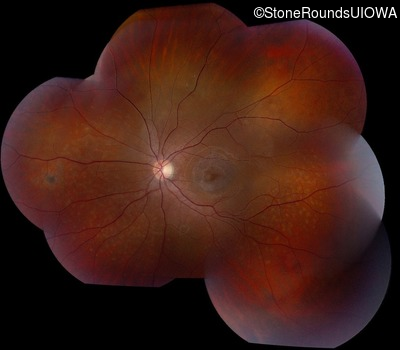

AR Stargardt Disease (IIA)

AR Stargardt Disease (IIA)

| Age at visit: 12 years |

| Age at visit: 13 years |

| Age at visit: 15 years |